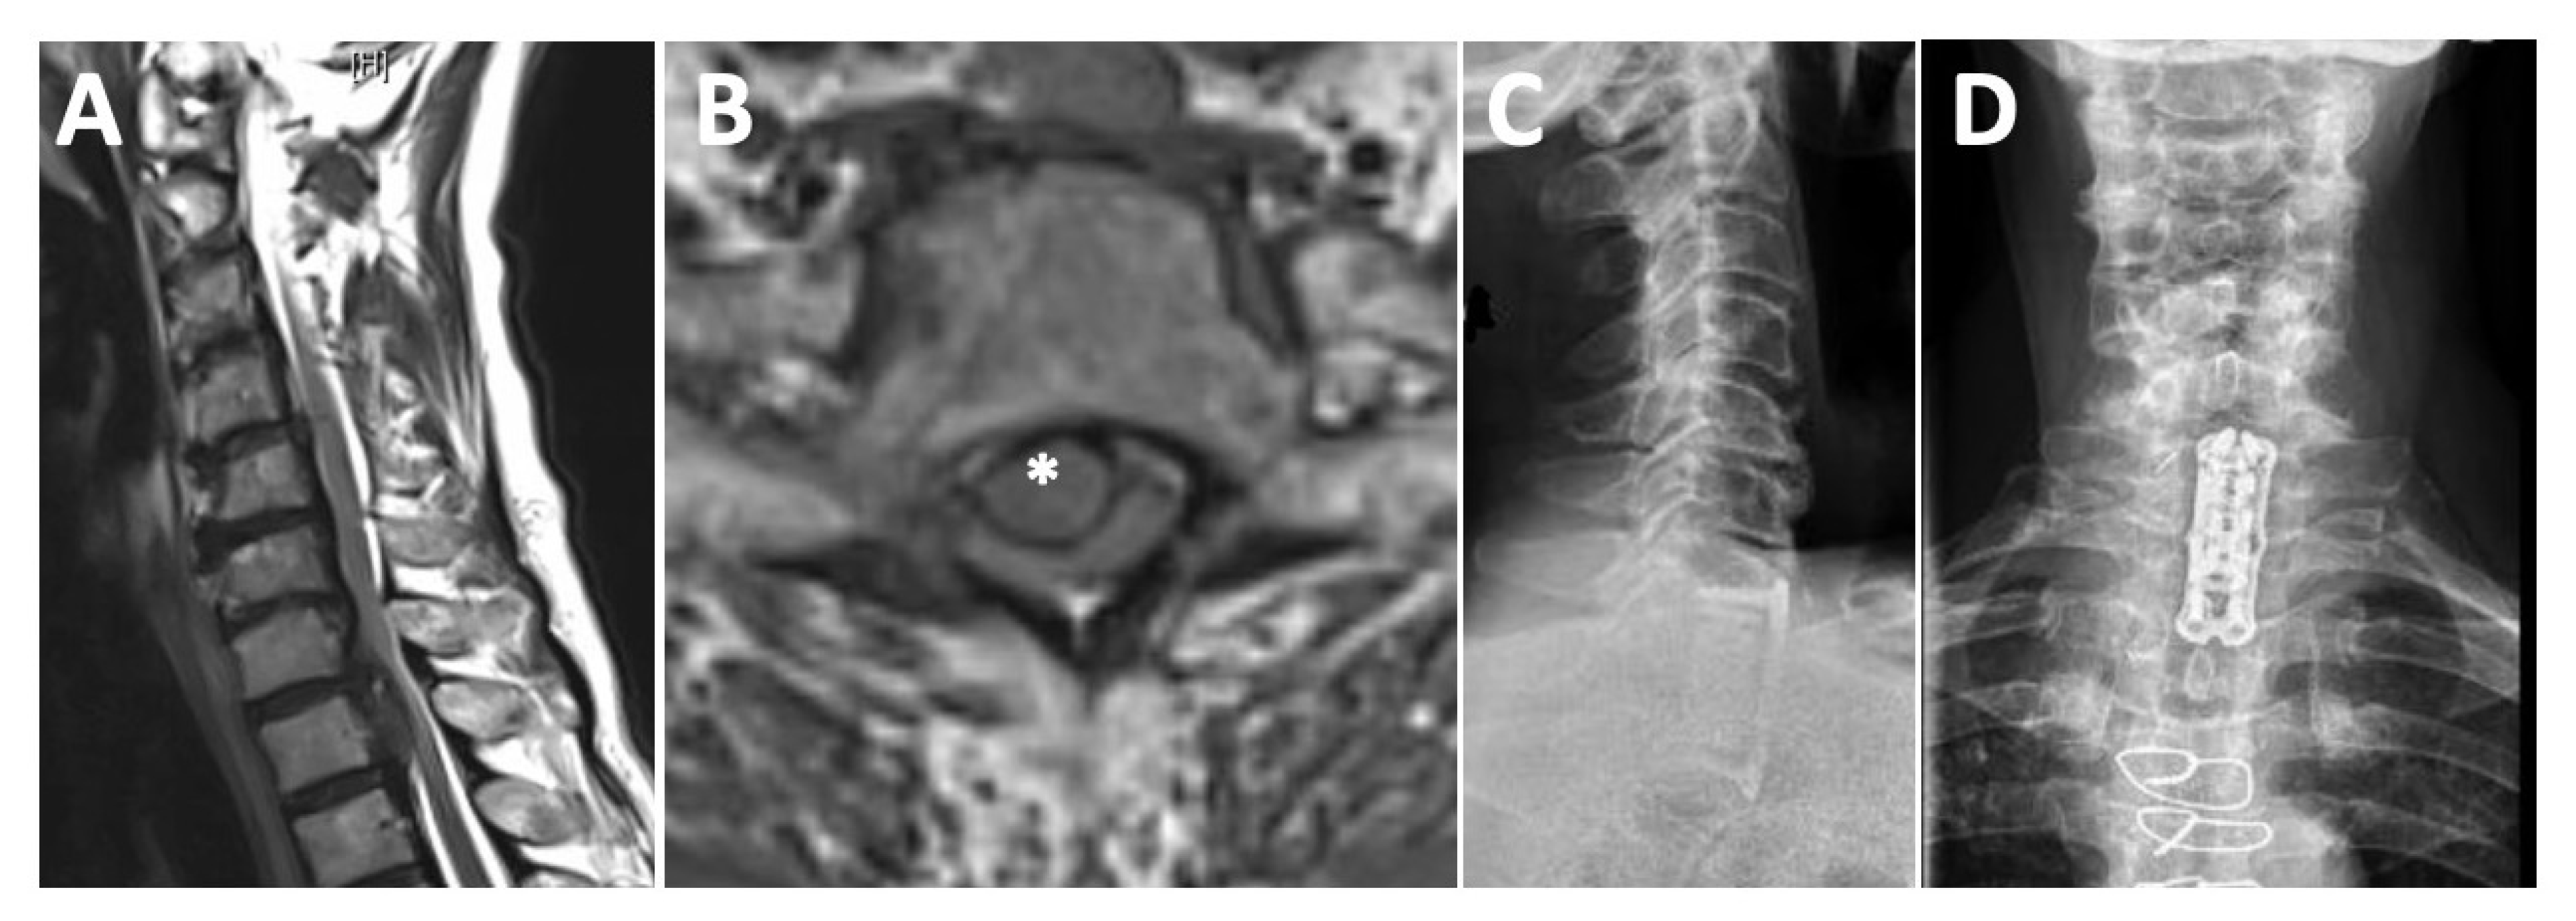

A 74-year-old female patient presented with a 2-month history of progressive spinal ataxia of the lower extremities, midback pain, and myelopathic signs with decreased sensation distributed below T2. After lifting a heavy weight, symptoms deteriorated. MRI revealed a C7/T1 central disc herniation with severe spinal cord compression and acute myelopathy (Figure 2A,B). The CT showed extended calcifications of the herniated disc sub-totally occupying the spinal canal. The patient was treated via an anterior approach with partial sternotomy, C7 and T1 corpectomy, and microsurgical decompression of the spinal canal. Vertebra replacement was achieved with an expandable cage and anterior plating in a standalone concept. Postoperatively, the patient experienced immediate relief of her myelopathic symptoms and was able to walk without assistance by postoperative day 7. At 3 months follow-up, the patient reported complete symptom relief with no residual back pain. Figure 3 shows the preoperative MRI and the postoperative X-ray.

Figure 3.

Junctional disc herniation. Preoperative T2-weighted MRI in sagittal (A) and axial (B) orientation showing a large C7/T1 central disc herniation with caudal extension to T2, severe spinal cord compression, and acute myelopathy (herniated disk is highlighted by * in (B)). Postoperative X-ray in lateral (C) and anterior-posterior (D) view, confirming excellent implant position after standalone anterior treatment.